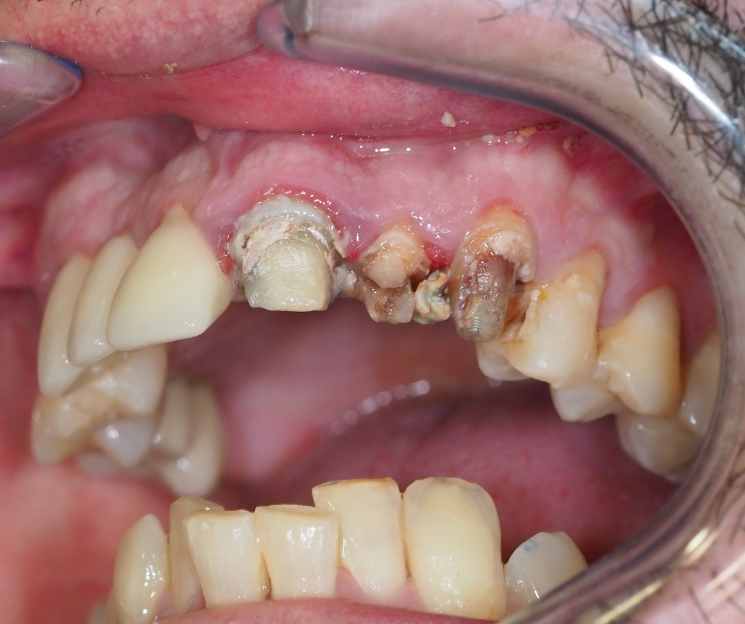

Extracción de piezas 21, 22 y 23 con infección activa

Paciente con infecciones de origen dental que comprometían severamente el hueso alveolar en la zona anterior superior. Se realizó la extracción de los dientes 21, 22 y 23, y se optó por una rehabilitación inmediata mediante implantes córticobasales.